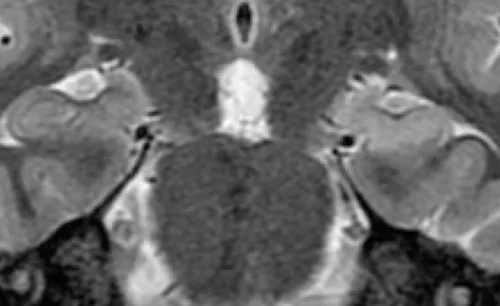

MRI examination of the brain, close-up image showing left hippocampal sclerosis.

Epilepsy treatment is most effective when the onset of the seizure can be specifically localized to one or more origins within the brain. MRI collects structural information and creates images of the brain by using a large magnet. It is the most important imaging modality for epilepsy evaluation. Because of its critical role in management, MRI should be performed using a state-of-the-art 3 tesla MRI scanner according to technically specific scan protocols. The MRI should also interpreted by subspecialty-certified neuroradiologists with expertise in epilepsy.